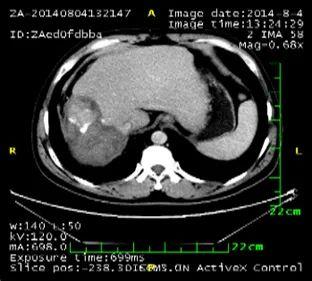

淫羊藿素软胶囊治疗后的影像学变化

1. 肝脏原发病灶治疗前后磁共振扫描结果对比

淫羊藿素软胶囊治疗3、6、16、18个月后,肝脏病变呈现消融后改变,未观察到病灶进展。

治疗前